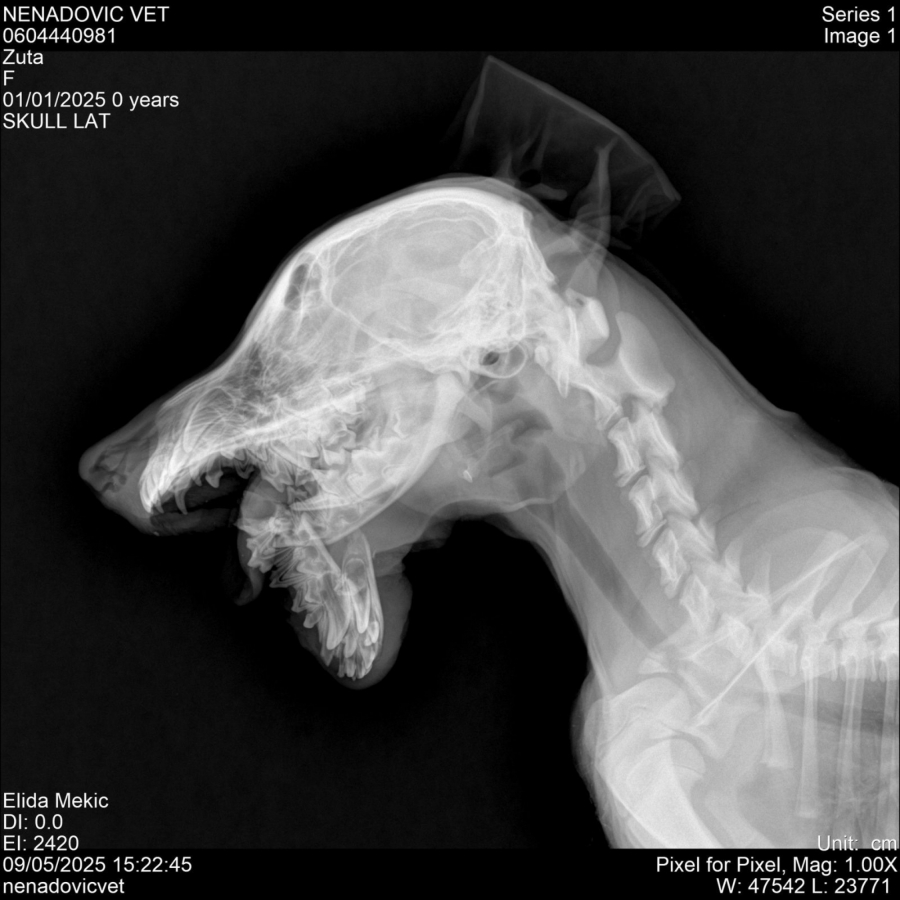

BRUTALNO PRETUČENO ŠTENE, SLOMLJENA MU VILICA Horor u Prijepolju, kakav čovek mora da bude da uradi OVO?

- Slomljena mu je vilica. Nije udareno kolima, nije doživelo nesreću — ovo je delo čoveka. Svesno. Namerno. Bezdušno. Zar živimo među onima koji su sposobni da ovako nešto urade? Zar ćemo i dalje ćutati dok se nasilje oko nas normalizuje? Ovo nije samo napad na jedno bespomoćno biće, ovo je opomena — jer ko je sposoban da ovako povredi štene, sposoban je da povredi i čoveka, kaže za RINU Anes Muzurović.

On dodaje da je zahvaljujući Elidi M. iz Prijepolja, štene zbrinuto i hitno odvedeno na operaciju.